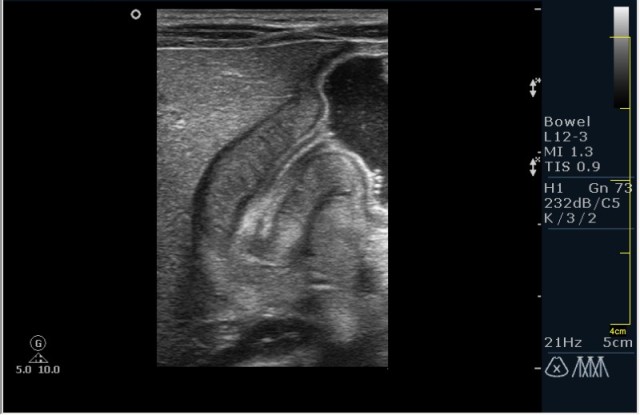

а у нас сегодня опять одна красава! (месяца 3 НИОДНОГО пилоростеноза небыло!)

34647.JPG

34648.JPG

сорри, колесико недотянула